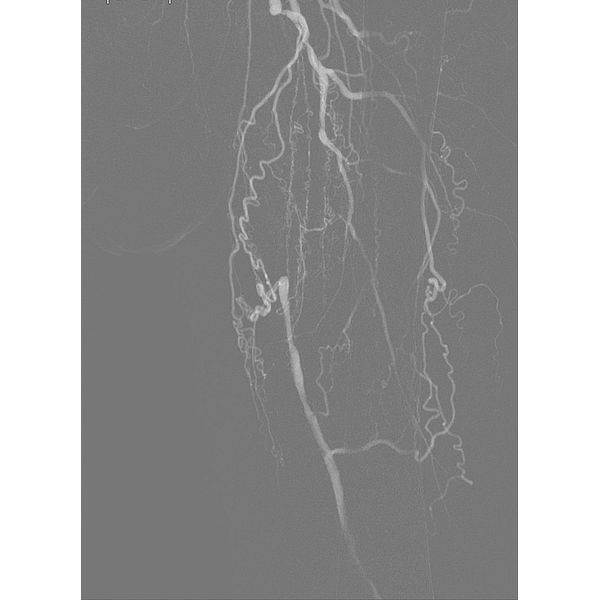

Когда пациент поступил в больницу, ему провели КТ-ангиографию ног, на которой обнаружили окклюзию бедренно-подколенного артериального сегмента и артерий голени слева.

У мужчины диагностировали:

- трофическая язва;

- атеросклероз артерий ног;

- окклюзию бедренно-подколенного артериального сегмента и артерий голени слева;

- хроническую ишемию ног (ХИНК) IV степени.